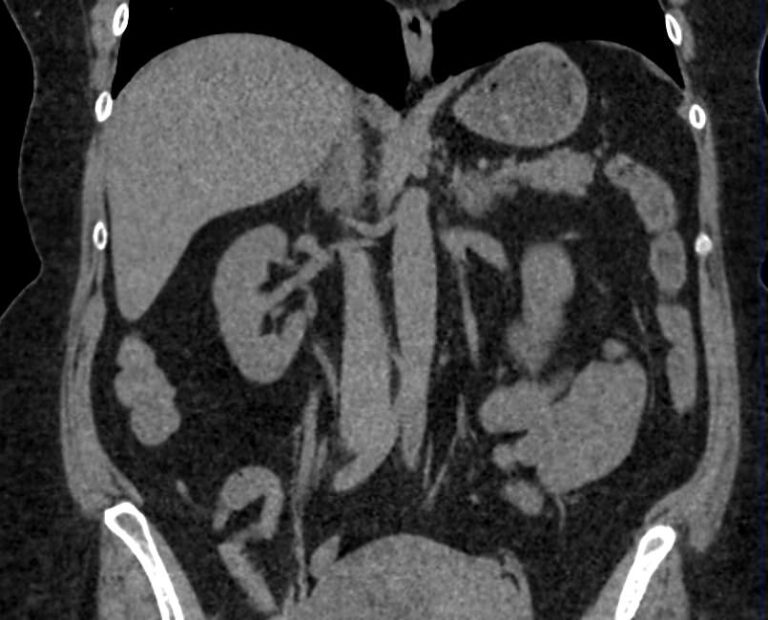

Мультиспиральная компьютерная томография (МСКТ) брюшной полости относится к современным лучевым методам исследования, с помощью которого можно оценить состояние органов брюшной полости (печени, желчного пузыря, поджелудочной железы, селезенки), прилегающих к ним кровеносных сосудов и лимфатических узлов.

С помощью мультиспиральной компьютерной томографии проводятся послойные рентгеновские снимки исследуемой области с толщиной среза от 0,5 мм. В нашей клинике исследование выполняется на компьютерном томографе экспертного класса TOSHIBA AQUILION CXL, который оснащен 128 детекторами, позволяющими получать за несколько секунд снимки брюшной полости с высокой точностью. Большое количество детекторов позволяет получить точные данные, при этом сократить время исследования и сделать минимальной лучевую нагрузку на пациента. Кроме того, инновационные технологии аппарата дают возможность сформировать объемную модель органа и окружающих структур, что также способствует проведению точной и достоверной диагностики.

При подозрении на опухоли, воспалительные процессы, гнойные очаги назначается КТ брюшной полости с внутривенным болюсным контрастированием. Для этого пациенту внутривенно вводится рентгеноконтрастное вещество на основе йода. Благодаря усиленному кровоснабжению препарат накапливается в структуре патологических образований и помогает врачу-рентгенологу выявить изменения в структуре внутренних органов.

Метод контрастирования помогает максимально точно выявить очаг патологии уже на начальной стадии, а также установить его локализацию, точные размеры, форму и особенности кровоснабжения.